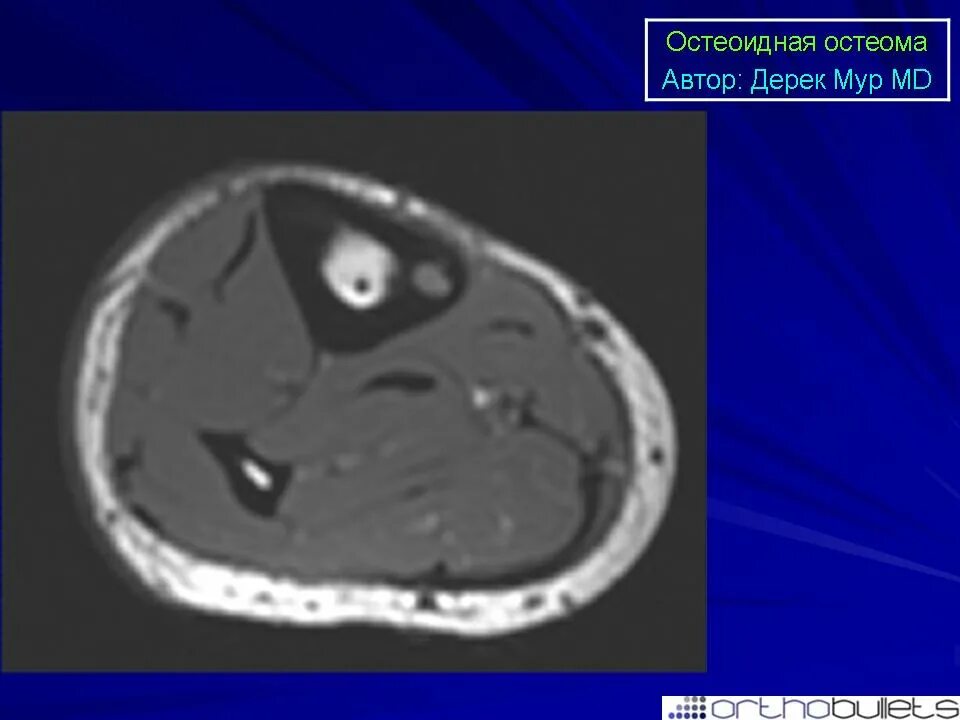

Остеома мрт